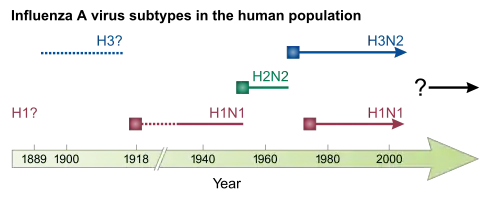

Este género tem apenas uma espécie, o Influenzavirus A. As aves aquáticas selvagens são o hospedeiro natural de uma grande diversidade de vírus de gripe A. Ocasionalmente, estes vírus são transmitidos para outras espécies e podem dar origem a surtos devastadores em aves de criação ou desencadear pandemias de gripe humana.[35] Os vírus do tipo A correspondem aos patógenos mais virulentos entre os três tipos de vírus da gripe e estão na origem das formas mais graves da doença. Os vírus da gripe A podem ser divididos em diferentes serotipos em função da resposta dos anticorpos a estes vírus.[36] Os serotipos confirmados em seres humanos, ordenados pelo número de mortes em pandemias, são:

- H1N1, que provocou a gripe espanhola em 1918, gripe russa de 1977 e a gripe suína em 2009

- H2N2, que provocou a Gripe asiática de 1957 e a Gripe russa em 1989-90

- H3N2, que provocou a gripe de Hong Kong em 1968

Os vírus de gripe evoluem continuamente, através de mutação ou recombinação.[36] As mutações podem provocar pequenas alterações nos antígenos hemaglutinina e neuraminidase na superfície do vírus. Estas alterações denominam-se deriva antigénica, a qual vai lentamente criando uma cada vez maior variedade de estirpes até que se desenvolva uma que seja capaz de infetar pessoas imunes às estirpes anteriores. Esta nova variante substitui então as anteriores, à medida que se propaga rapidamente entre a população humana, muitas vezes causando uma epidemia.[150] No entanto, uma vez que as estirpes produzidas por deriva genética ainda têm algumas semelhanças com as estirpes mais antigas, algumas pessoas continuam a ser imunes. Por outro lado, quando os vírus de gripe se recombinam adquirem antígenos completamente novos, um processo que é denominado mudança antigénica. Se for produzido um vírus de gripe humano com antígenos completamente novos, toda a população estará susceptível e o novo vírus dissemina-se de forma incontrolável, dando origem a uma pandemia.[151] No entanto, tem também vindo a ser proposta uma abordagem alternativa a este modelo de pandemia baseado em mudanças e derivas antigénicas, o qual sustenta que as pandemias periódicas são produzidas pelas interações de um conjunto fixo de estirpes humanas, sendo a população humana que ciclicamente adapta a sua imunidade às diferentes estirpes desse conjunto.[152]

As pandemias posteriores não foram tão devastadoras. Entre elas estão a Gripe Asiática de 1957 (tipo A, estirpe H2N2) e a Gripe de Hong Kong de 1968 (tipo A, estirpe H3N2), as quais, embora de menor dimensão, foram responsáveis pela morte de milhões de pessoas. A gripe russa de 1977 causou 700.000 mortes em todo o mundo.[171][172] Nas pandemias mais recentes estavam disponíveis fármacos para controlar as infeções secundárias, o que pode ter ajudado a reduzir a mortalidade em comparação com pandemias anteriores.[169]